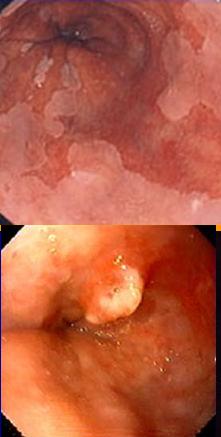

Image

precancereuse a la jonction muqueuse . A inferieure

bourgeon pre-cancereuse |

Endobrachyoesophagede Barrett. Stenose

legere a la jonction de muqueuse gastrique et

muqueuse oesophagien |